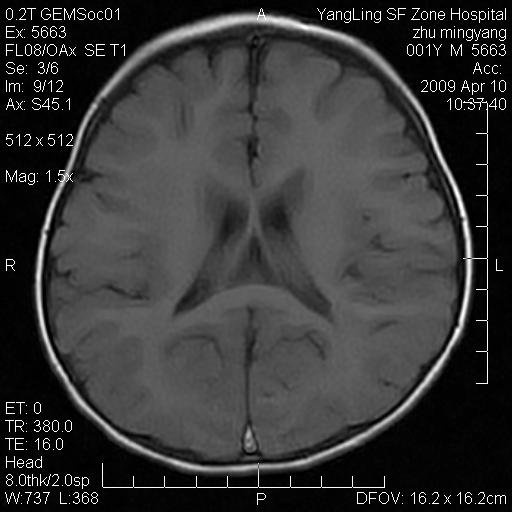

患者:1岁半,两天前外伤收住我院,ct检查小脑占位

考虑星形细胞瘤,建议增强

髓母细胞瘤或血管母细胞瘤,增强后可以鉴别;影像资料见 <。鱼博浪老师的《中枢神经系统ct与mr鉴别诊断》 小脑部肿瘤章节。

髓母细胞瘤或血管母细胞瘤!支持!

支持考虑髓母细胞瘤

考虑----髓母细胞瘤可能性大

考虑髓母细胞瘤或室管膜瘤。

支持髓母细胞瘤。

考虑髓母细胞瘤。

考虑髓母细胞瘤或星形细胞瘤

考虑髓母细胞瘤.

考虑髓母细胞瘤可能性大。

小脑肿瘤.考虑髓母细胞瘤可能.

就病灶部位及临床资料首先考虑髓母.